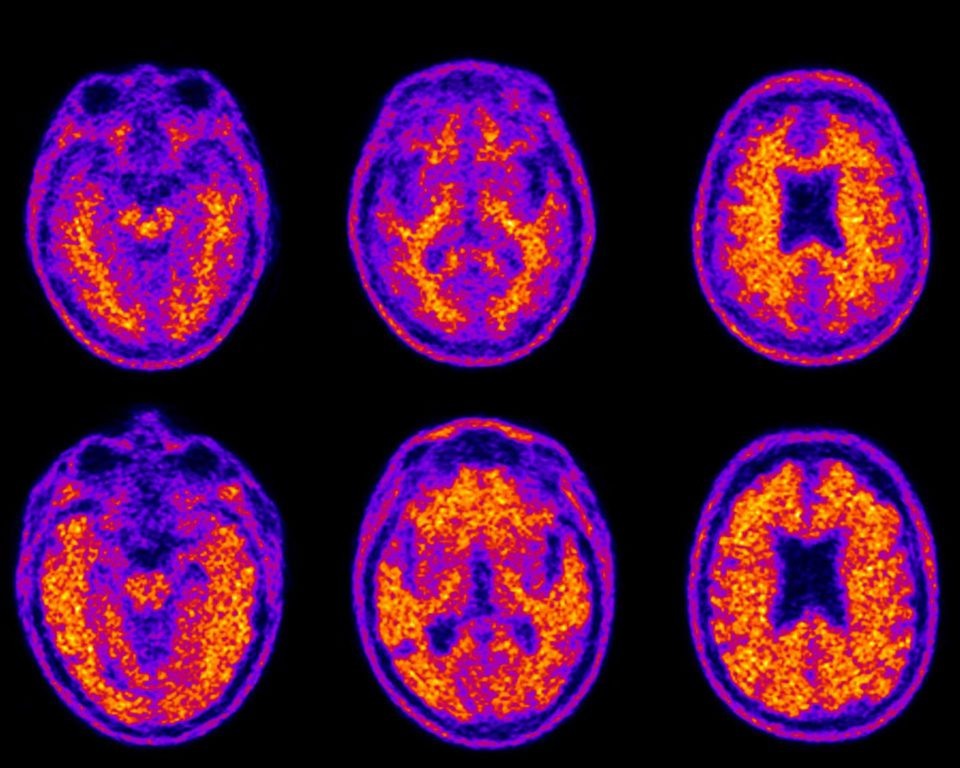

Credit:S. Tolbert et al. / Theournal of Prevention of Alzheimer’s Disease 2019

Результаты основаны на данных 243 взрослых людей в среднем возрасте от 55 до 90 лет, которые участвовали в исследовании. Оно включало в себя тесты на финансовые навыки и ПЭТ-сканирование мозга со специальным веществом флорбетапиром (18F-Florbetapir) для выявления амилоидных бляшек. В них принимали участие как здоровые люди, так и больные с нарушениями памяти – как легкими, так и тяжелыми.